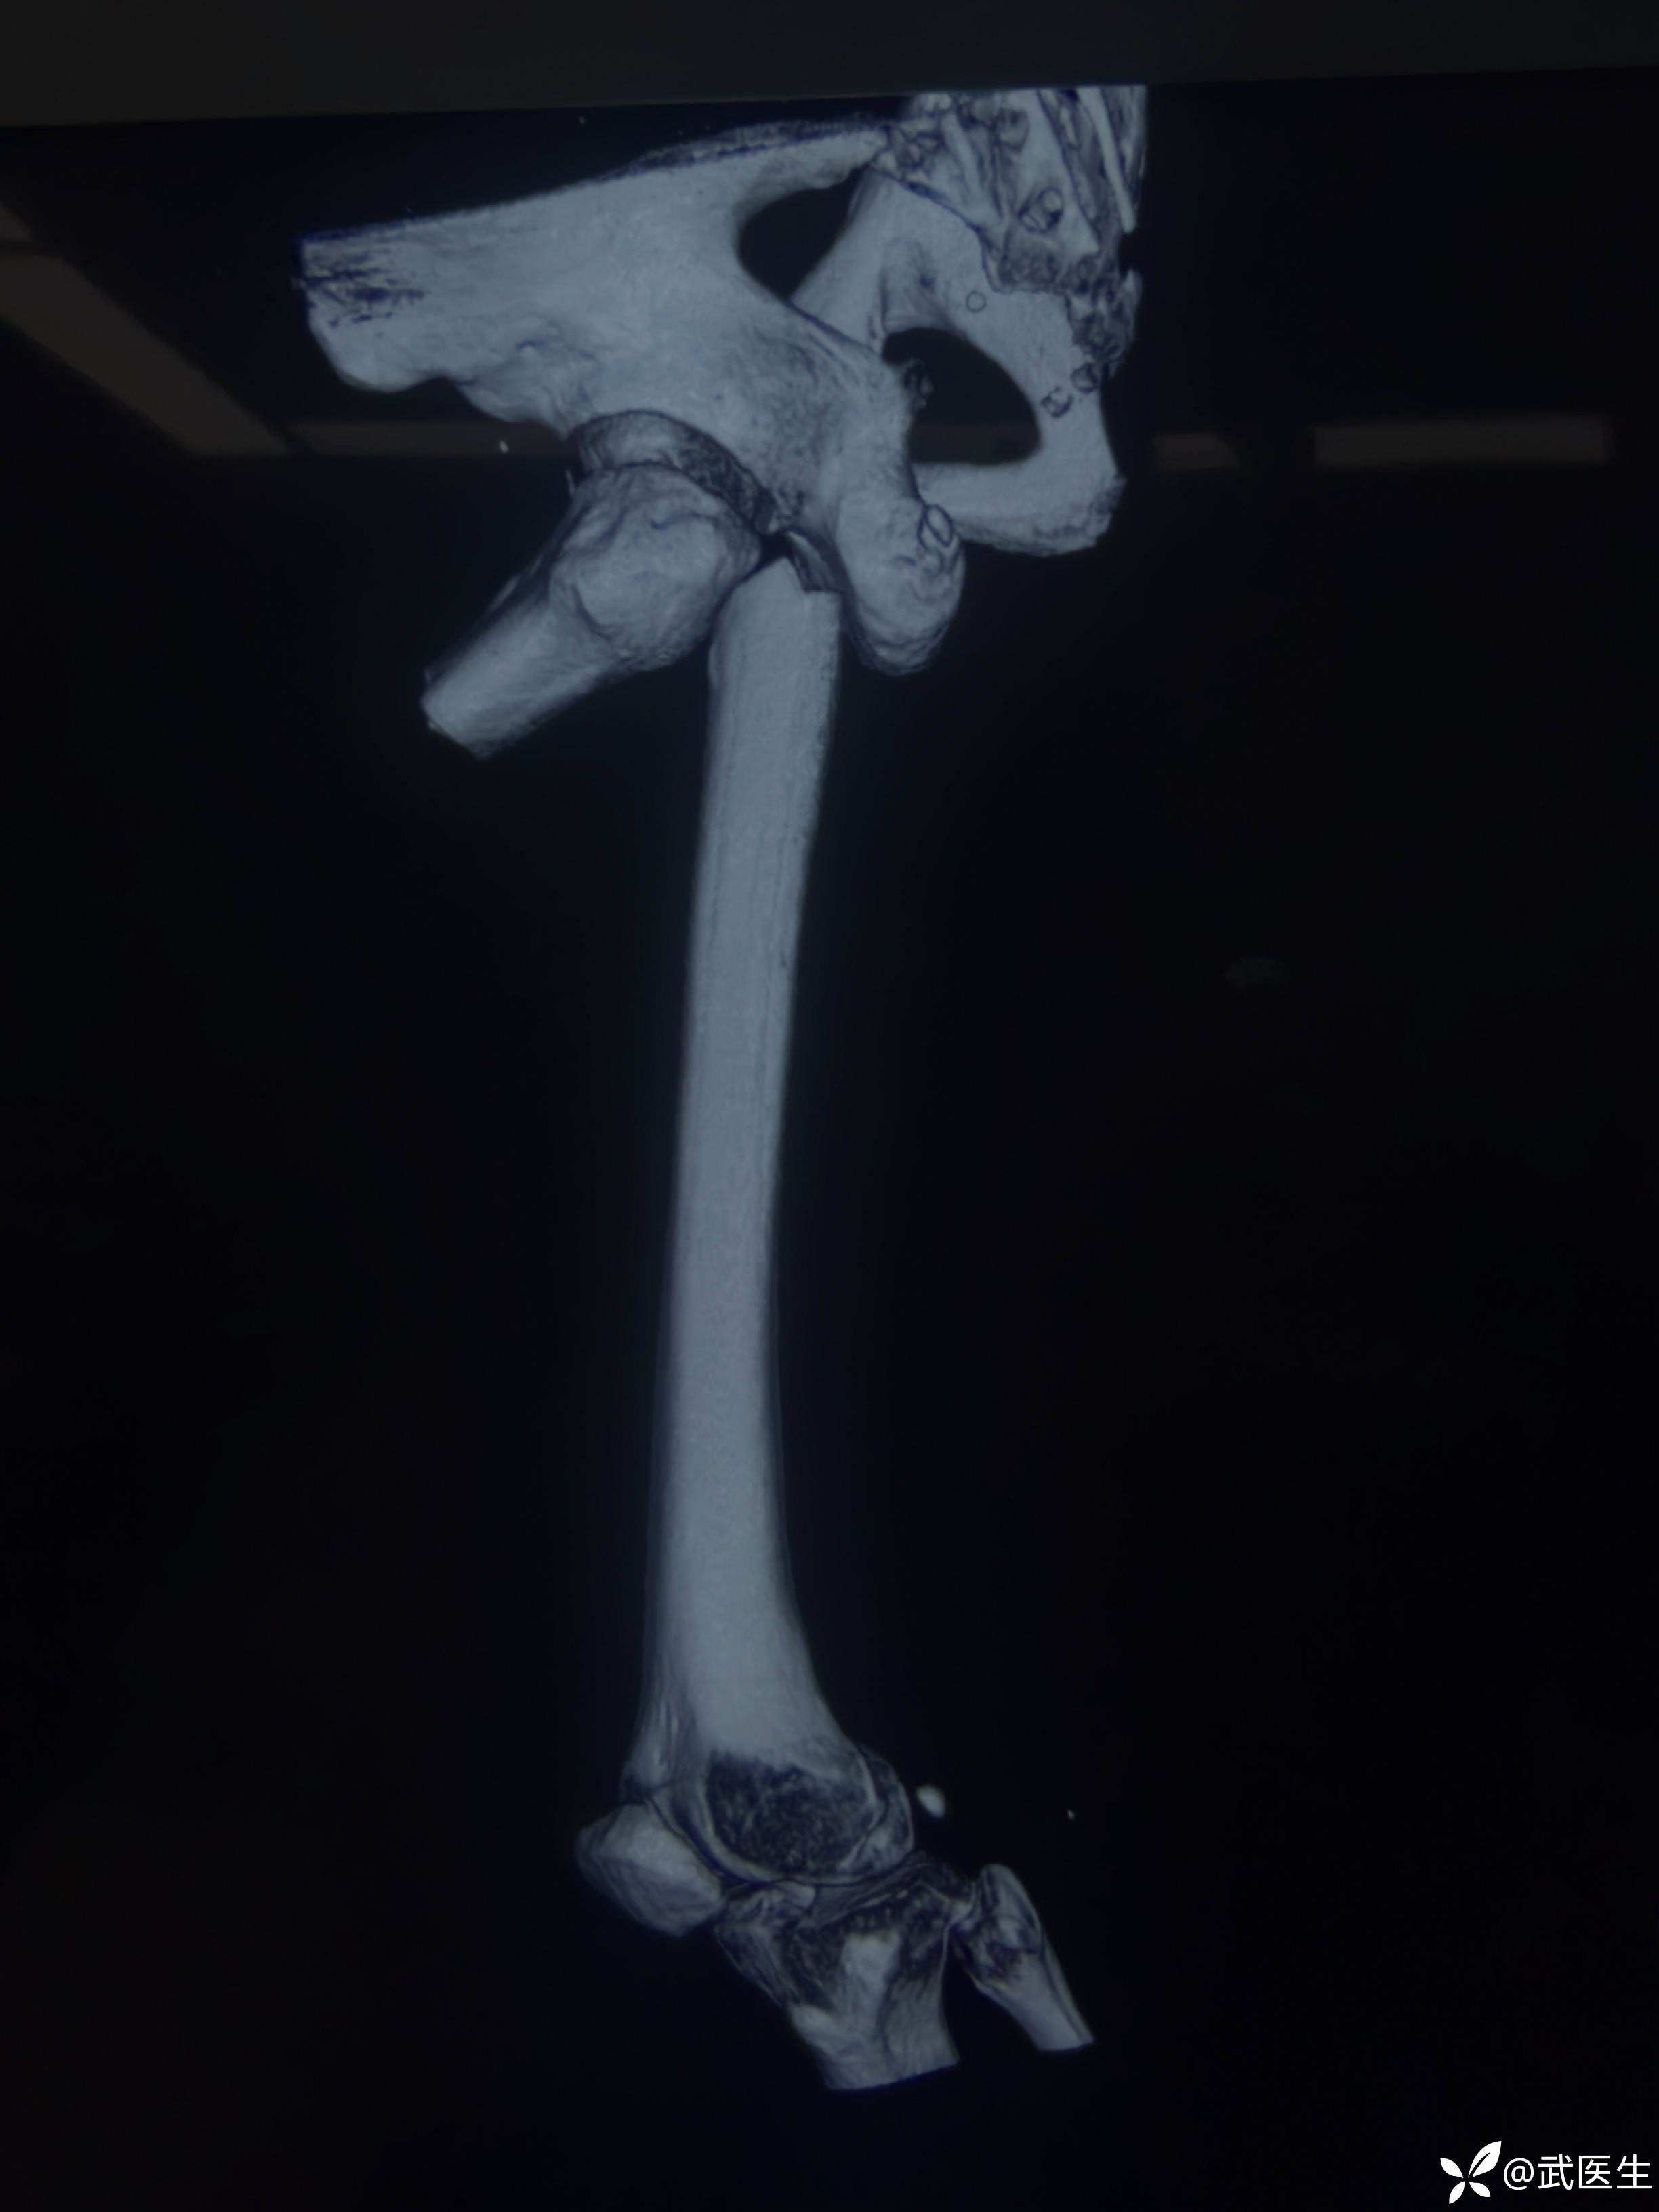

分享一例髓内钉治疗股骨近端骨折病例

男,66岁,摔伤致左大腿疼痛活动受限三小时就诊,门诊以“左股骨干骨折”为诊断收住入院,上图

股骨近端骨折,老先生挺瘦,很奇怪的是,大腿几乎无肿胀,入院后骨牵引,老先生也没怎么感觉骨折部位特别疼痛。